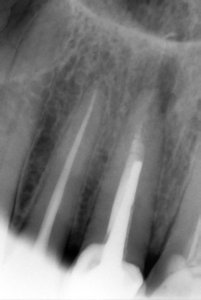

Сегодня сделала рентген пазух, сказали, что все хорошо. Прицельный снимок 14,15 и 16 зуба есть, посмотрите, пожалуйста. Там над зубами большие чёрные пятна. Скажите, а на 26 зубе кисто-гранулема, врач не назначала снимков перед реставрацией и вкрутила штифт, а там уже была кисто-гранулема до пломбировки, она мне его сделала. А другая стоматолог сказала, что не надо его заново читать далее

• Претензии Вы можете выставить, но при наличии документального подтверждения лечения (чеки или квитанции, договор и гарантийный талон). В противном случае ― это бесполезно. На снимке я не вижу ярко выраженных симптомов грануляции. Затемнение в пазухах, вполне может быть наложением при снимке. Необходим нормальный снимок, либо прицел на физиографе, либо К/Т. После можно окончат читать далее